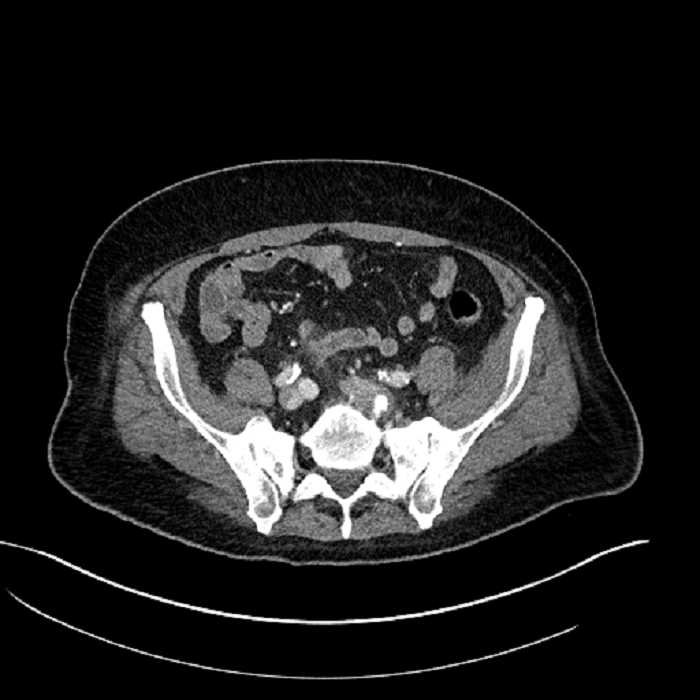

• Mild mural thickening of a segment of the sigmoid colon with adjacent fat stranding and a 1.5 cm fluid and gas collection along the tip of an inflamed diverticulum

• Loss of the normal fat plane between this collection and adjacent loops of small bowel, which demonstrate mural thickening

• No bowel obstruction

Acute sigmoid diverticulitis complicated by a small contained perforation and a large abscess in the right hepatic lobe. Additional small subcapsular abscesses along the anterior margin of the left hepatic lobe.

Additionally, loss of the normal fat plane between the peridiverticular collection and adjacent thickened loops of small bowel raises the potential for an enterocolonic fistula.

Hepatic abscess showing the double target sign with low density internally surrounded by a thin inner enhancing rim (red arrow) and ill-defined outer low density rim (yellow arrow). Blue arrow indicates an internal septation. Red arrows: additional smaller subcapsular abscesses. Red arrow: focal contained perforation associated with diverticulitis.